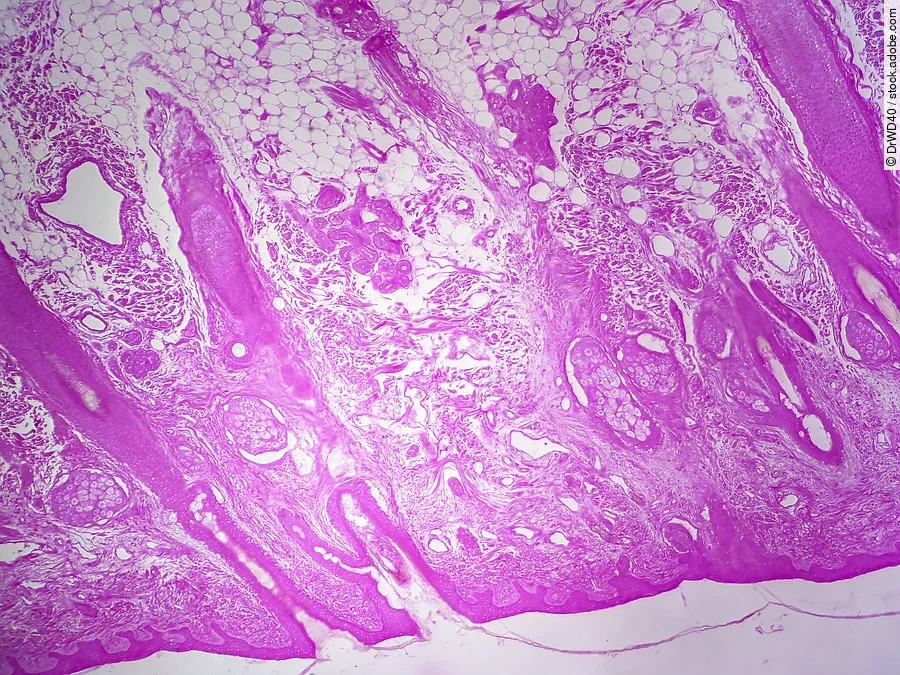

Das Vollhaut-Äquivalent aus dem Labor ist mit echter Hundehaut nahezu identisch. Damit lassen sich aussagekräftige und präzise Tests von medizinischen Wirkstoffen durchführen. Ebenso lässt sich die Verträglichkeit marktüblicher Pflegeprodukte wie Shampoos oder Seifen damit testen. Auch sie können im Zweifelsfall der Hundehaut schaden, da die oberste Schutzschicht der Haut, die Epidermis, bei Hunden deutlich dünner als bei Menschen ist und auch kaum verhornt.

»Die Suche nach der richtigen Zusammensetzung der Enzyme und Medien benötigte eine ganze Reihe von Versuchen« sagt Dr. Burger-Kentischer. Doch am Ende ist sie perfekt gelungen. Das Vollhaut-Äquivalent aus dem Labor ist unter dem Mikroskop kaum von echter Hundehaut zu unterscheiden.